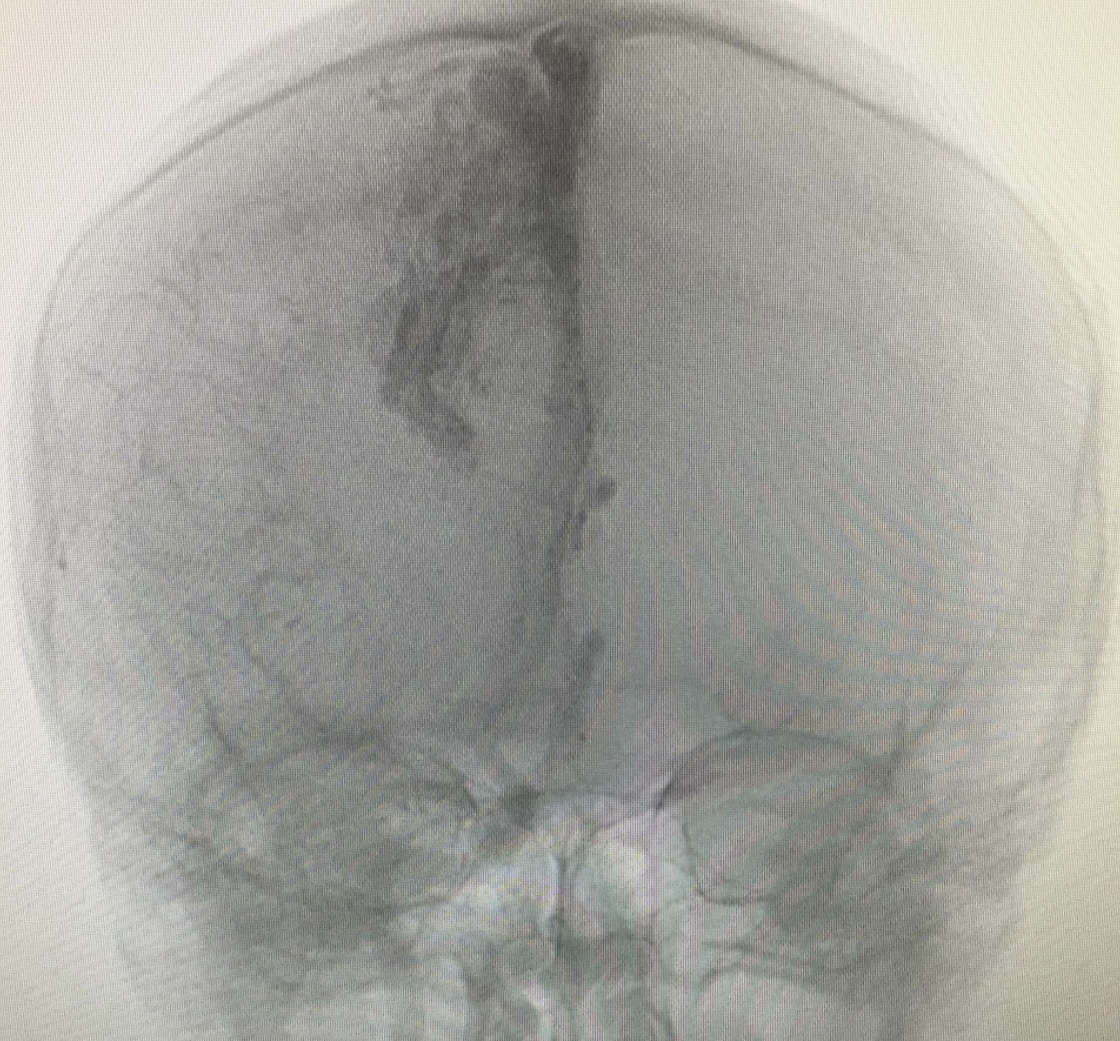

This is a photo of the first time I saw my AVM!

My neurologist referred to it has “medium-large” at 3.5cm x 1.7cm. It bunkers down towards the right motor cortex region of the brain. However, when I had my 3 bleeds, they were situated closer to the top of the brain, closer to the temporal lobe.

I remember at the time I was 19 and decided to take this picture because you can see my skull and I thought that was so cool! It really helped me absorb the impact of the news that this thing was causing the pressure in my brain. I look at it once and a while.

I personally use this picture to see how far I’ve come and how much left I have to overcome, and what I have to live with. To me it’s a symbol of patience in a way. I hope that makes sense!